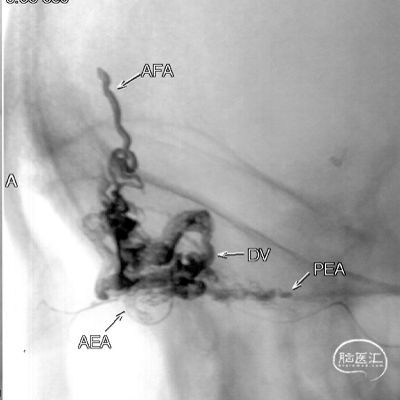

Onyx胶铸型进一步显示了瘘的结构。AFA:镰前动脉;AEA:筛前动脉;PEA:筛后动脉;DV:引流静脉。

Marathon微导管在Hybrid0.007微导丝导引下经左侧眼动脉超选至左侧筛前动脉,接近瘘口。

通过Marathon微导管超选造影,显示微导管楔入到靠近瘘口的动脉端。

通过Marathon微导管注入Onyx 18,胶向瘘口弥散,并弥散至镰前动脉。

停顿后进一步注射Onyx18,此时胶向对侧筛前动脉弥散,直至闭塞瘘口和引流静脉起始端。

最终造影瘘口完全不显影。